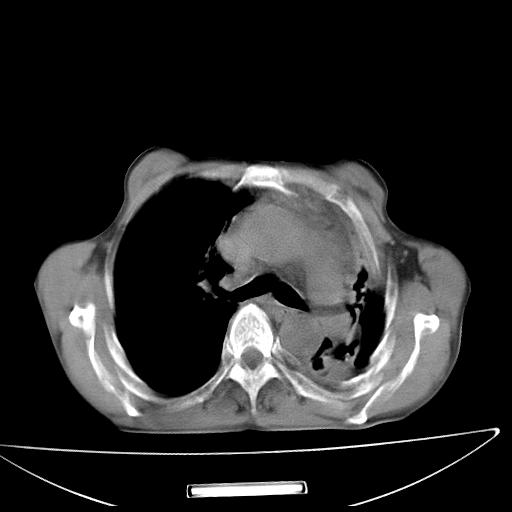

男  70岁,发烧咳嗽4天。盗汗,消瘦。无痰中带血丝,以前有肺tb病史,ct见,双肺tb,左侧胸廓塌陷,左胸膜肥厚粘连。纵隔移位,右侧胸腔积液,大家说说那个心影前左肺舌叶除了肺大炮还有炎症还是干酪性肺炎?有占位吗?我看纵隔淋巴结也大。

是胃,纵膈未见明显肿大淋巴结。

1)两肺继发性肺结核并左肺上叶肺不张,支气管扩张。2)双侧胸膜炎(胸膜增厚+少量胸腔积液)。

两肺继发性肺结核并感染,左肺上叶肺不张。建议ct增强。